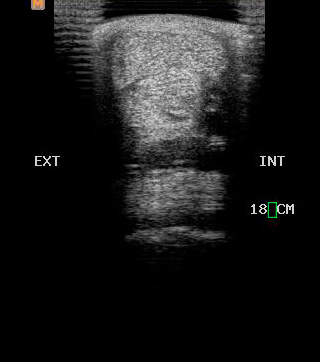

Ecografía

Cuenta con Ecografía digital de alta complejidad.

17 años de experiencia siendo una de las ecografistas más reconocidas en la práctica de equinos. Realiza pasantías en la universidad de Davis California y en Mid-Atlantic Equine Medical Center en New Jersey.